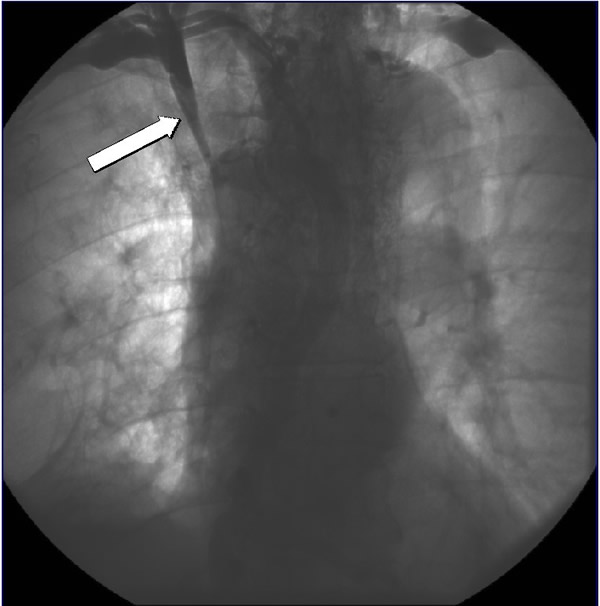

His physical examination was significant for head and upper extremity swelling, jugular venous distention without A or V waves, and superficial varices over the thorax. A computerized tomography (CT) scan (Figures 1A and 1B) demonstrated a mass in the mediastinum involving the superior vena cava (SVC) and extending into the right atrium. Echocardiography confirmed the intracardiac component. The patient was started on neoadjuvant therapy consisting of cisplatin, cyclophosphamide, and doxorubicin with plans for postoperative radiation therapy. A post chemotherapy CT scan demonstrated shrinkage of the mass (Figures 1C and 1D). A preoperative venogram confirmed the occluded SVC and well formed collaterals (Figure 2).

The patient was taken to the operating room and sternotomy performed after division of several large collateral chest wall veins. The pericardium was opened and resection of all thymic tissue was undertaken starting at the diaphragm (Figure 3). The SVC was transected at the confluence of the right subclavian and jugular veins and found to be filled with fibrotic tissue (Figure 4A). Frozen section examination of the luminal contents identified benign fibrotic tissue. The SVC was mobilized to the level of the right atrium en-bloc with the tumor, the azygos vein was divided, and a wedge resection of the medial aspect of the right upper lobe was performed. At this point, the tumor had been completely mobilized except for an intravascular extension through the SVC into the right atrium (Figure 4B).